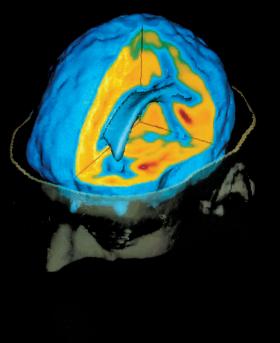

Upowszechnienie neuroobrazowania w latach 90. ubiegłego wieku przyczyniło się do poszerzenia wiedzy o ludzkim mózgu w kilku aspektach. Upowszechnienie neuroobrazowania w latach 90. ubiegłego wieku przyczyniło się do poszerzenia wiedzy o ludzkim mózgu w kilku aspektach. nimon_t / Smarterpix/PantherMedia

Komputerowe analizy danych pochodzących ze skanerów mózgu zawierają błędy.Steger Photo/Getty Images Komputerowe analizy danych pochodzących ze skanerów mózgu zawierają błędy.

Czym jest fMRI? Metoda ta zaczęła być powszechnie stosowana przez naukowców w latach 90. XX w., a swoją popularność zyskała dzięki możliwości bezinwazyjnego zaglądania do mózgu człowieka i przypatrywania się jego aktywności w trakcie np. rozwiązywania jakichś problemów czy oglądania zdjęć ukazujących przemoc.

Tym, co owe urządzenia bezpośrednio mierzą, nie jest jednak aktywność elektryczna komórek nerwowych, tylko sygnał zależny od poziomu nasycenia tlenem krwi (w skrócie BOLD, od blood-oxygen-level-dependent). Pomiar taki jest możliwy, gdyż utlenowana krew reaguje na silne pole magnetyczne wytwarzane przez potężne magnesy skanera.

Zasada działania jest tu stosunkowo prosta: obszary mózgu, które zaangażowane są w wykonywanie jakichś zadań, pracują intensywniej i z tego powodu zgłaszają zapotrzebowanie na więcej „paliwa”, czyli właśnie tlenu.